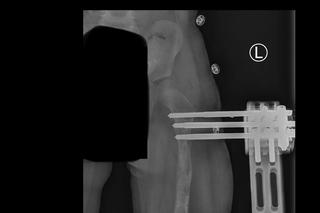

Zosia Szustakowska - to córeczka policjantów z wielkopolskiej i poznańskiej drogówki. Dziewczynka urodziła się z chorą, krótszą nóżką. Rodzice od razu postanowili zawalczyć o jej zdrowie. Dziewczynka przeszła trzy operacje wydłużenia nóżki. Pierwszą operację - biodra - była dwa lata temu. Kolejną operacją było wydłużenie kości udowej - noga Zosieńki została wydłużona prawie o 6 cm.

Chociaż wszystko wydawało się już być na dobrej drodze, 8 maja, w trakcie szpitalnej konsultacji okazało się, że jest potrzebny kolejny, pilny i bardzo kosztowny zabieg - osteotomia miednicy. Rodzice Zosi - Magda i Daniel muszą teraz uzbierać ogromną kwotę 120 tys. zł, aby Zosia mogła odzyskać sprawność!

Operację wykonuje polski zespół z kliniki Paley European Institute, a lekarzem prowadzącym Zosię jest nieoceniony doktor Tomasz Albrewczyński. Zosi można pomóc TUTAJ. Liczy się każda, nawet najdrobniejsza wpłata.